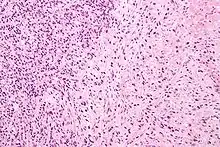

![]() Gleason grade — Lower grades are associated with small, closely packed glands. Cells spread out and lose glandular architecture as grade increases. Gleason score is calculated from grade as described in the text. |

A pathologist microscopically examines the biopsy specimen for certain "Gleason" patterns. These Gleason patterns are associated with the following features:

- Pattern 1 - The cancerous prostate closely resembles normal prostate tissue. The glands are small, well-formed, and closely packed. This corresponds to a well differentiated carcinoma.

- Pattern 2 - The tissue still has well-formed glands, but they are larger and have more tissue between them, implying that the stroma has increased. This also corresponds to a moderately differentiated carcinoma.

- Pattern 3 - The tissue still has recognizable glands, but the cells are darker. At high magnification, some of these cells have left the glands and are beginning to invade the surrounding tissue or having an infiltrative pattern. This corresponds to a moderately differentiated carcinoma.

- Pattern 4 - The tissue has few recognizable glands. Many cells are invading the surrounding tissue in neoplastic clumps. This corresponds to a poorly differentiated carcinoma.

- Pattern 5 - The tissue does not have any or only a few recognizable glands. There are often just sheets of cells throughout the surrounding tissue. This corresponds to an anaplastic carcinoma.

In the present form of the Gleason system, prostate cancer of Gleason patterns 1 and 2 are rarely seen. Gleason pattern 3 is by far the most common.

The Gleason grade is based on tissue architectural patterns rather than purely cytological changes. These tissue patterns are classified into 5 grades, numbered 1 though 5. Lower numbers indicate more differentiation, with pattern 5 being the least differentiated.[4][7] Differentiation is the degree to which the tissue, in this case the tumor, resembles native tissue. Greater resemblance (lower grade) is typically associated with a better prognosis.